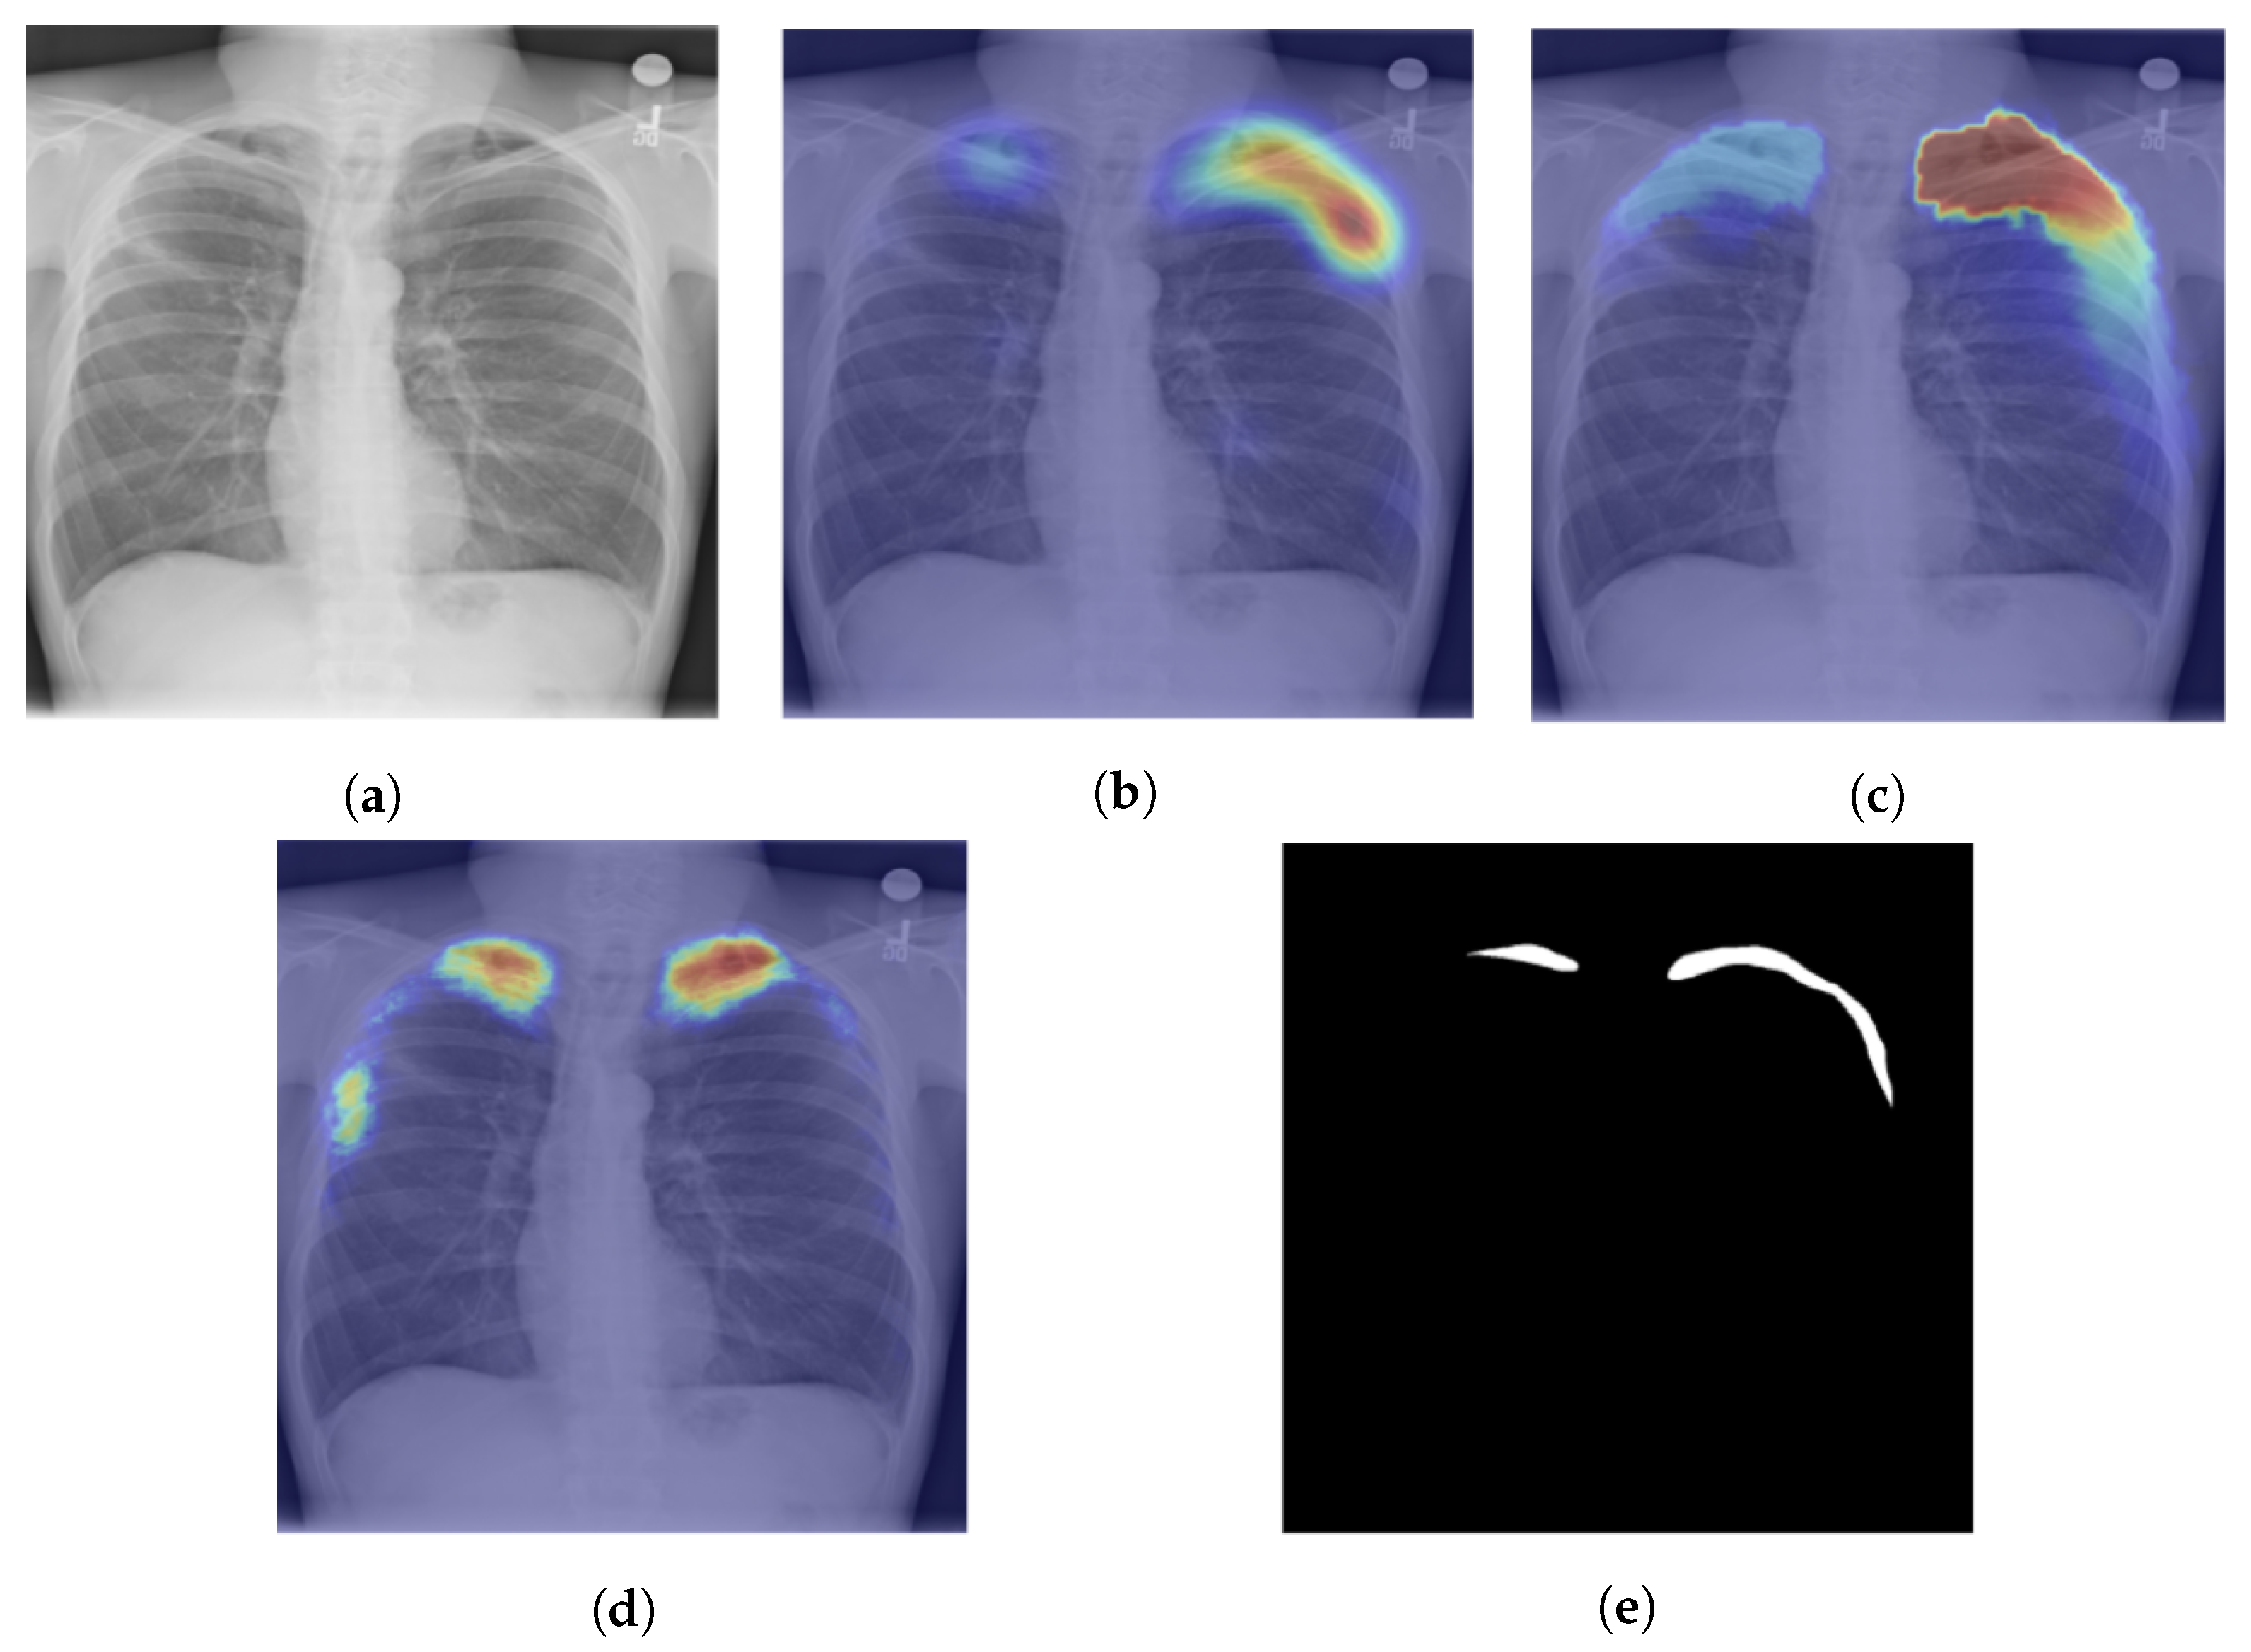

| Seda et al., 2018 [103] | ChestX-ray14 | Multiscale attention map and layer relevance weights |

| Singh et al., 2020 [106] | The posteroanterior CXRs from Christian Medical College in Vellore, India | Multiscale attention map |

- Sedai, S.; Mahapatra, D.; Ge, Z.; Chakravorty, R.; Garnavi, R. Deep multiscale convolutional feature learning for weakly supervised localization of chest pathologies in X-ray images. In Proceedings of the International Workshop on Machine Learning in Medical Imaging, Granada, Spain, 16 September 2018; pp. 267–275. [Google Scholar]